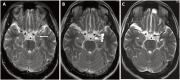

Results: Secondary brain tumors occurred in 21% of cases: 10% were cavernomas, 6% were meningiomas, 3% were skull osteomas, and 1% were anaplastic astrocytoma. The cumulative proportion of developing secondary brain tumor was 6% at 10 years and 20% at 20 years, while the cumulative proportion for developing cavernomas and meningiomas was 16% and 7% at 20 years, respectively.

Conclusion: Our study shows that patients who received cranial irradiation were at risk of secondary brain tumors such as cavernomas and meningiomas. Thus, a meticulous follow-up of cancer survivors with history of cranial irradiation by an annual MRI scan is justifiable. This will help clinicians to detect secondary brain tumors early and make its management much easier.